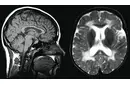

Beyinde kitle ameliyatı, genellikle tümörler, kist veya diğer anormal oluşumların cerrahi olarak çıkarılması amacıyla yapılan bir işlemdir. Bu tür bir ameliyat, beyin dokusuna doğrudan müdahale gerektiği için belirli riskler taşır ve sonrasında hastalar için çeşitli zorluklar ortaya çıkabilir. İşte bu makalede, beyin kitle ameliyatının riskleri ve sonrası hakkında detaylı bir inceleme yapılacaktır. 1. Beyin Kitle Ameliyatının Riskleri Beyin kitle ameliyatı, birçok risk barındırır. Bu riskler arasında şunlar bulunmaktadır:

4. Potansiyel Komplikasyonlar Ameliyat sonrası komplikasyonlar, hastanın genel sağlığını etkileyebilir. Bunlar arasında: